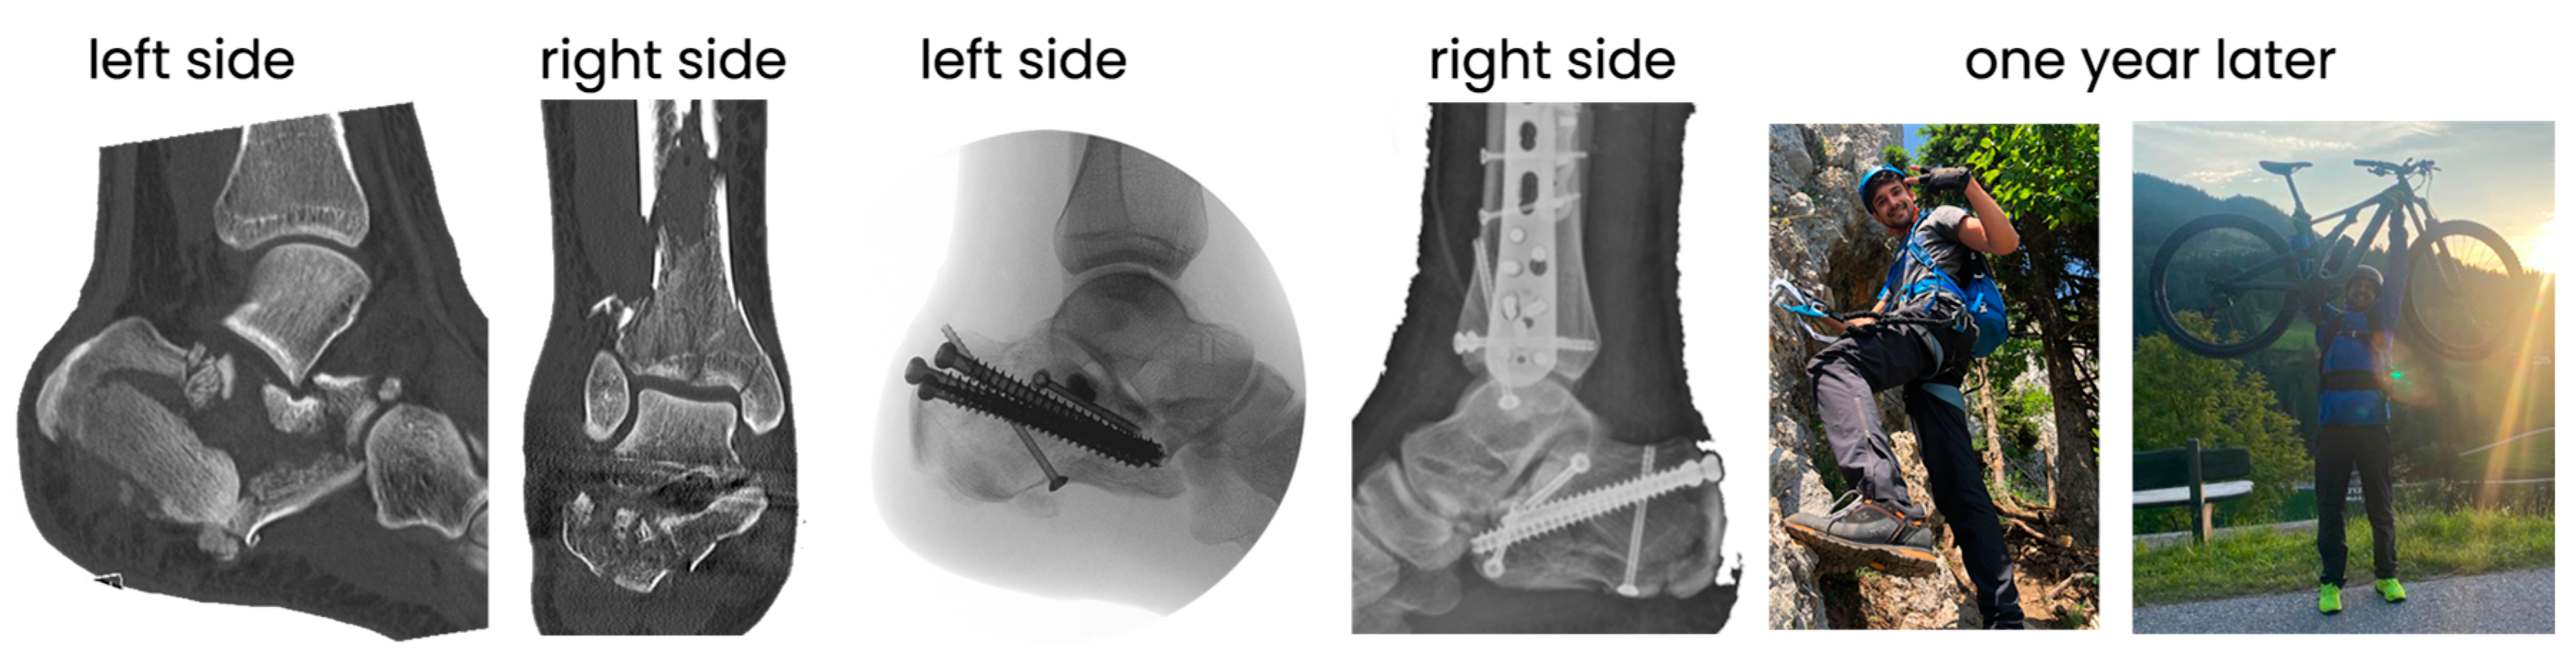

2.4. Method